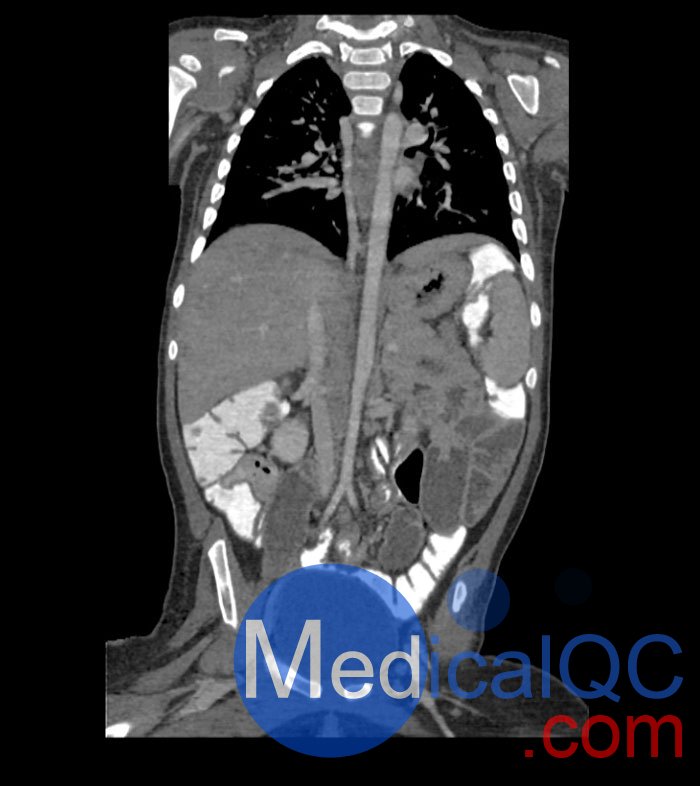

WEK58-03兒童軀干模型,WEK58-03兒童軀干模體模擬了 1 歲兒童的造影劑增強了門靜脈期的胸部、腹部和骨盆。它覆蓋了會陰的第六頸椎。結(jié)腸充滿造影劑,如直腸給藥后。

WEK58-03兒童軀干模型,WEK58-03兒童軀干模體提供了對軟組織和骨組織的詳細(xì)而逼真的模擬。包括肺在內(nèi)的空隙充滿了大約 -160HU的纖維素聚合物復(fù)合材料。

真實模擬脈管系統(tǒng)、骨骼和軟組織,包括肺、心臟、肝臟、膽囊、胰腺、脾臟、腎上腺、腎臟、胃、小腸、結(jié)腸和膀胱。

WEK58-03兒童軀干模型,WEK58-03兒童軀干模體成像效果圖:

SAG: